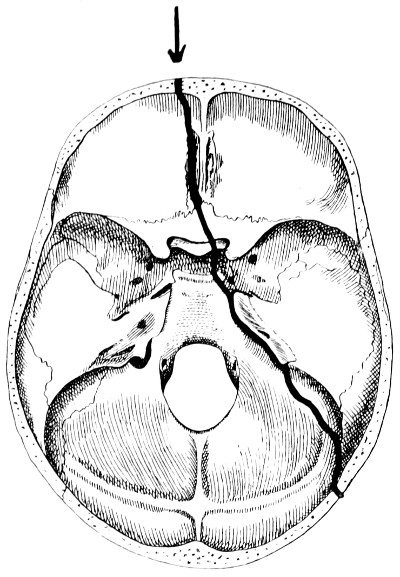

28. Illustrating the lines along which forces received on the vault are transmitted to the base 69

29 A and B. The base of the skull and the base as seen on transillumination 70, 71

30. Plan of the base of the skull 77

31. To illustrate the relation of basic fractures to cranial nerves 81

32-37. The lines pursued by basic fractures 83-8

38 A and B. To illustrate the probable source of profuse hæmorrhage from the ear 97